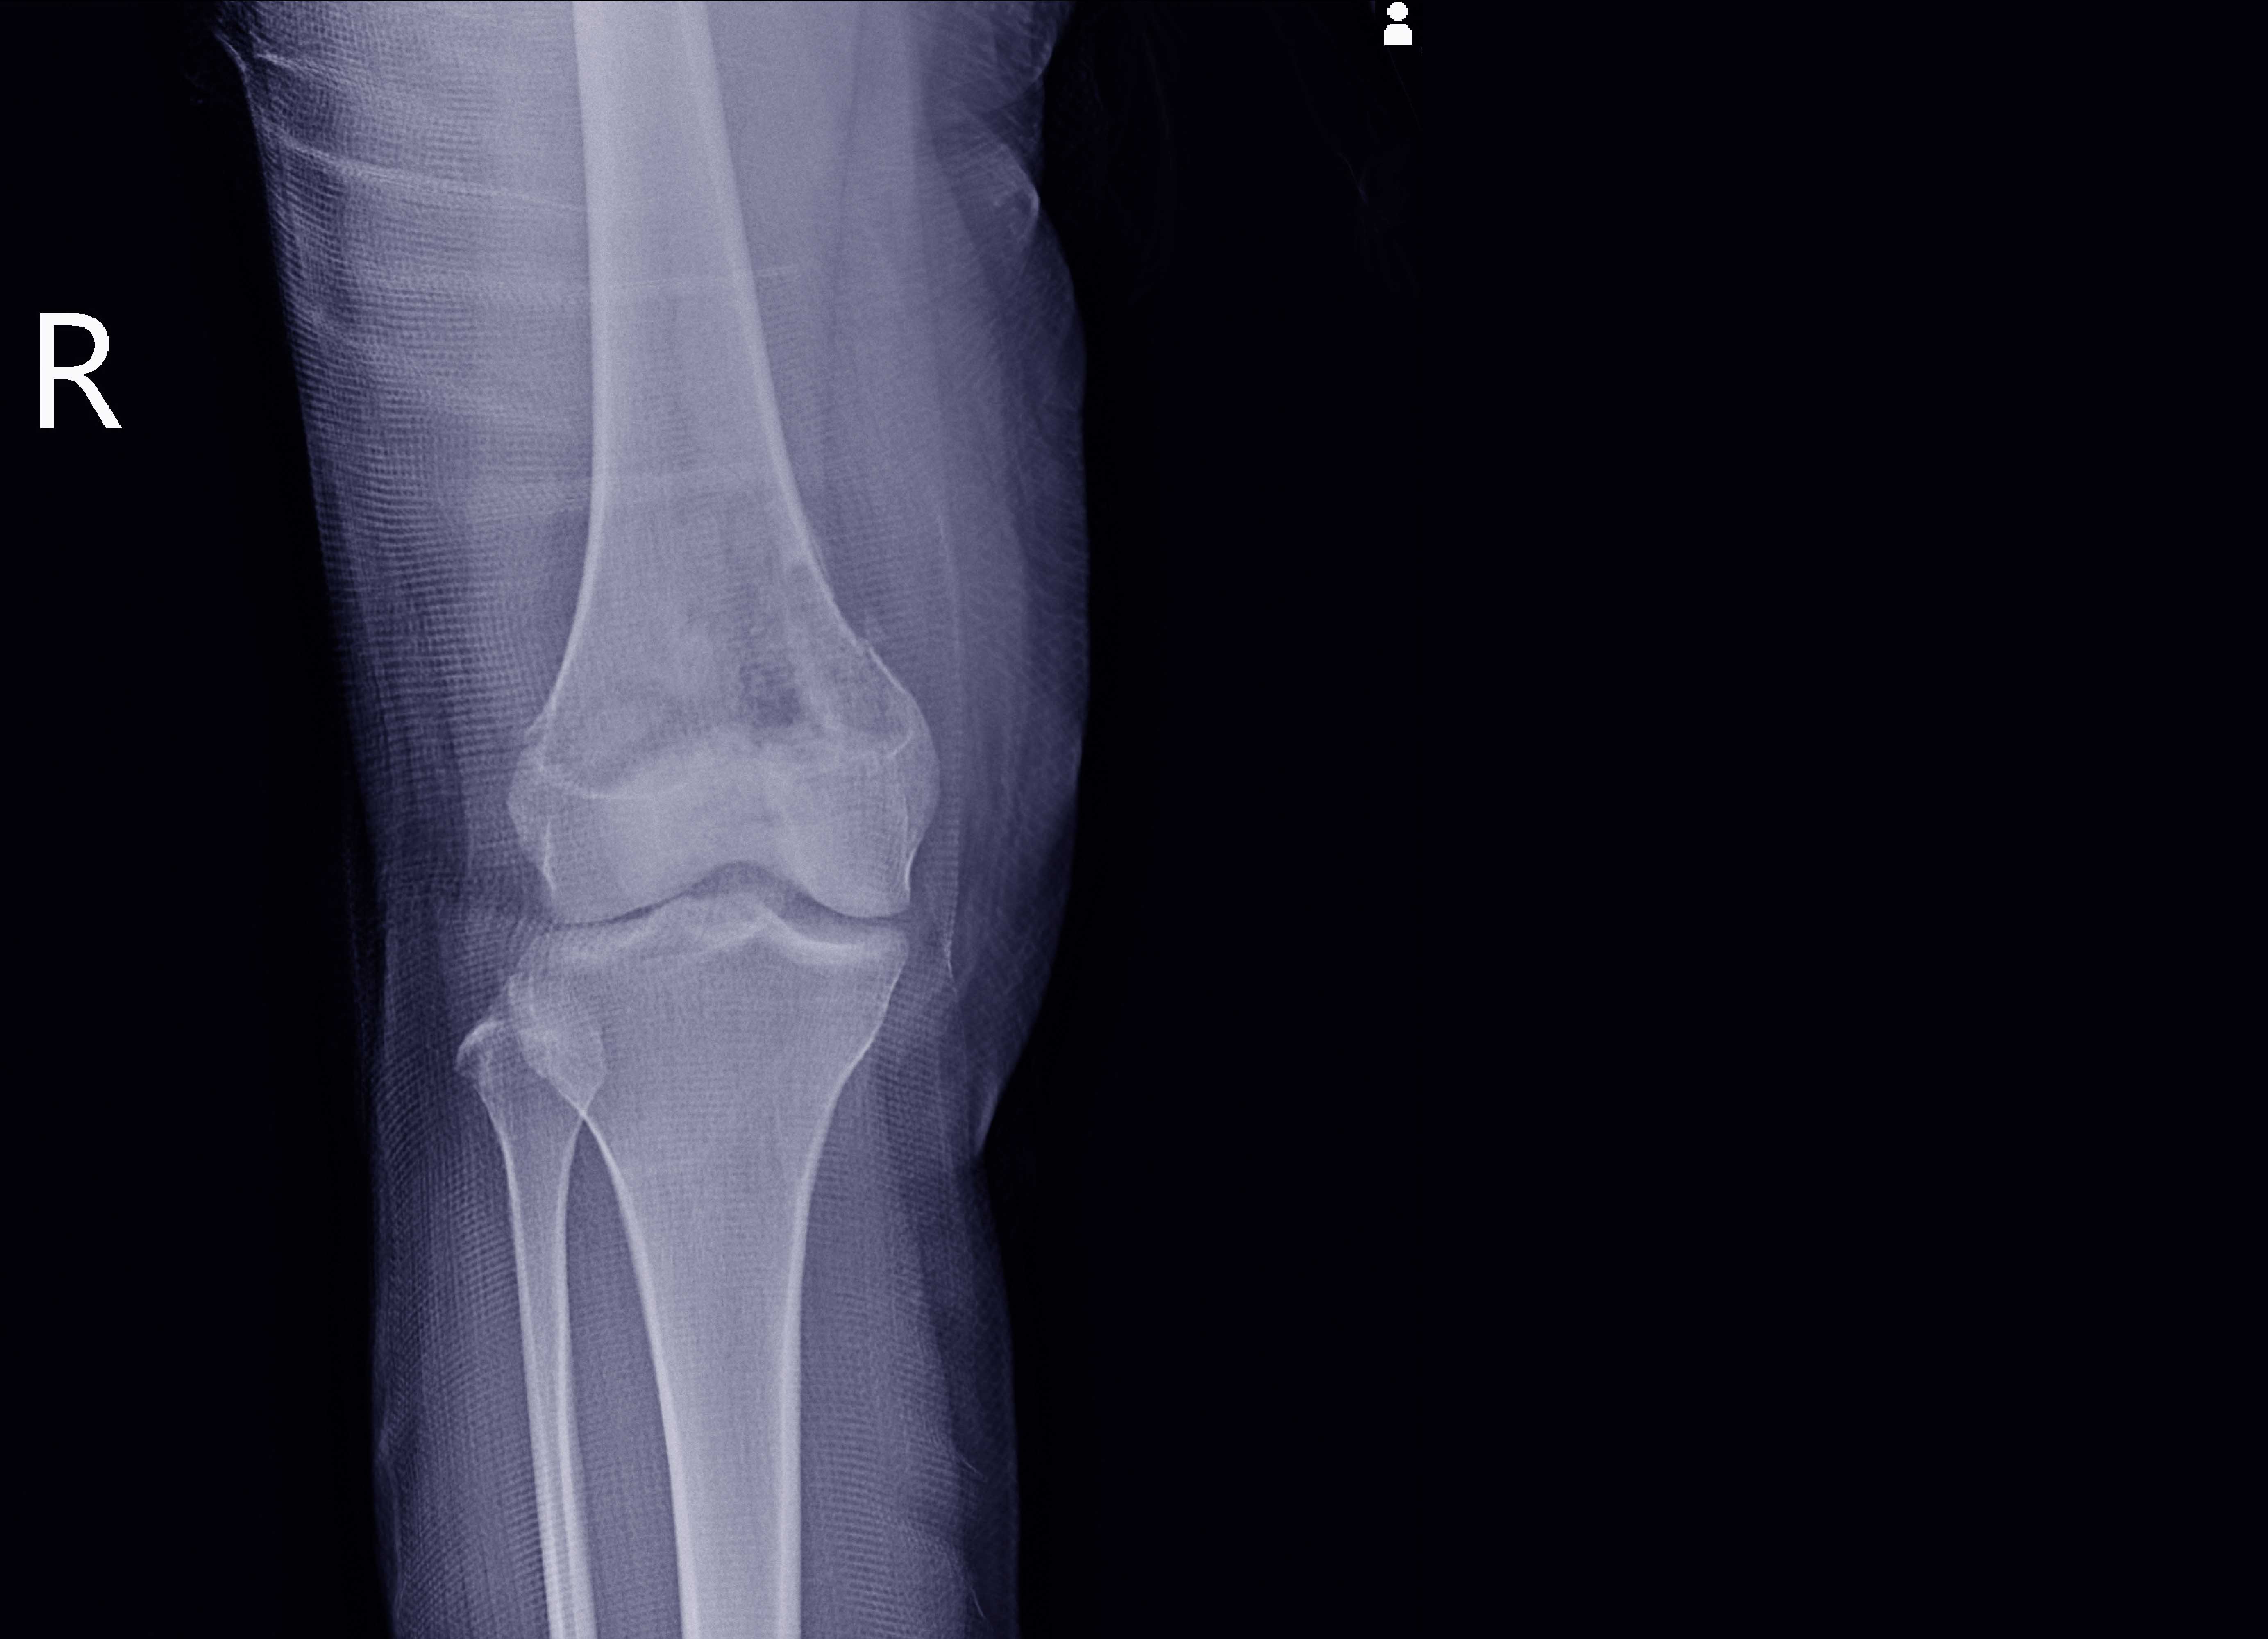

برنامج زمالة مدته عامان تم تصميمه لتوفير خبرة معمقة للأطباء الذين أتمّوا برنامج تدريب التشريح النسيجي الجراحي للأطباء المقيمين. ويركز التدريب على الجوانب العملية والأكاديمية والإدارية لممارسة التشريح النسيجي، من أجل إعداد طبيب تشريح نسيجي مؤهل بالكامل مع الاطلاع الموسّع على التخصص الفرعي للتشريح النسيجي للعظام والأنسجة الرخوية. وتقدم الإدارة خدمة فعالة للتشريح النسيجي للعظام والأنسجة الرخوية.

كما يتيح البرنامج فرصة للتقييم وللتعلم من كمّ متنوع للغاية من مواد علم الأمراض في مختلف جوانب أمراض العظام والأنسجة الرخوية. وعلاوة على ذلك، يتوفر للطبيب المتدرب الدعم والتوجيه من خلال الإشراف المهني وذلك لإجراء واحد أو أكثر من المشروعات البحثية.